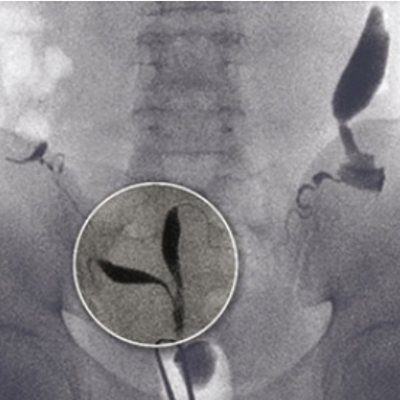

不妊患者におけるX線像

不妊患者852例中75例(8.8%)に脈管内侵入がみられましたが、臨床症状を呈したものはなく、アレルギー反応も認められませんでした。